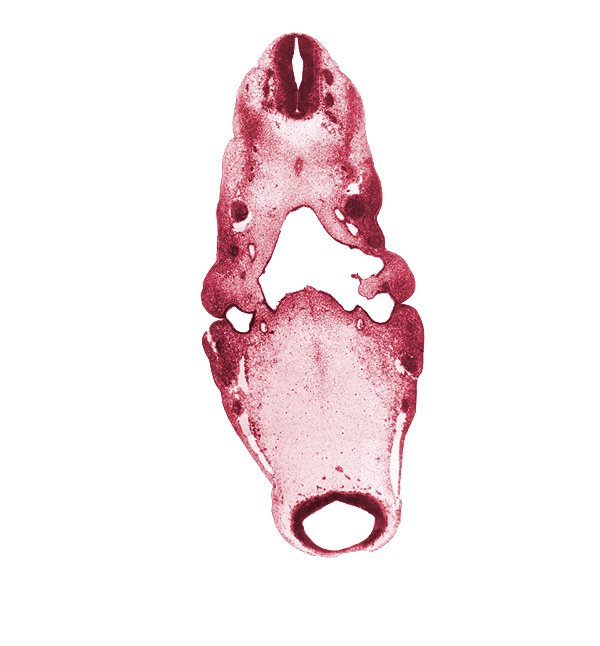

Carnegie Embryo #6502 | Location: 11-01-02

Keywords: caudal edge of C-1 spinal ganglion, dorsal aorta, hypoglossal nerve (CN XII), inferior ganglion of glossopharyngeal nerve (CN IX), inferior ganglion of vagus nerve (CN X), internal carotid artery, junction of precardinal and primary head veins, maxillary nerve (CN V₂), mesencephalon (M1), mesencoel (cerebral aqueduct), neural canal, notochord, ophthalmic nerve (CN V₁), pharyngeal arch 1, pharyngeal arch 2, pharyngeal pouch 1, pontine flexure region, posterior cerebral artery, primary maxillary vein, spinal accessory nerve (CN XI), stem of anterior dural venous plexus

Source: The Virtual Human Embryo.